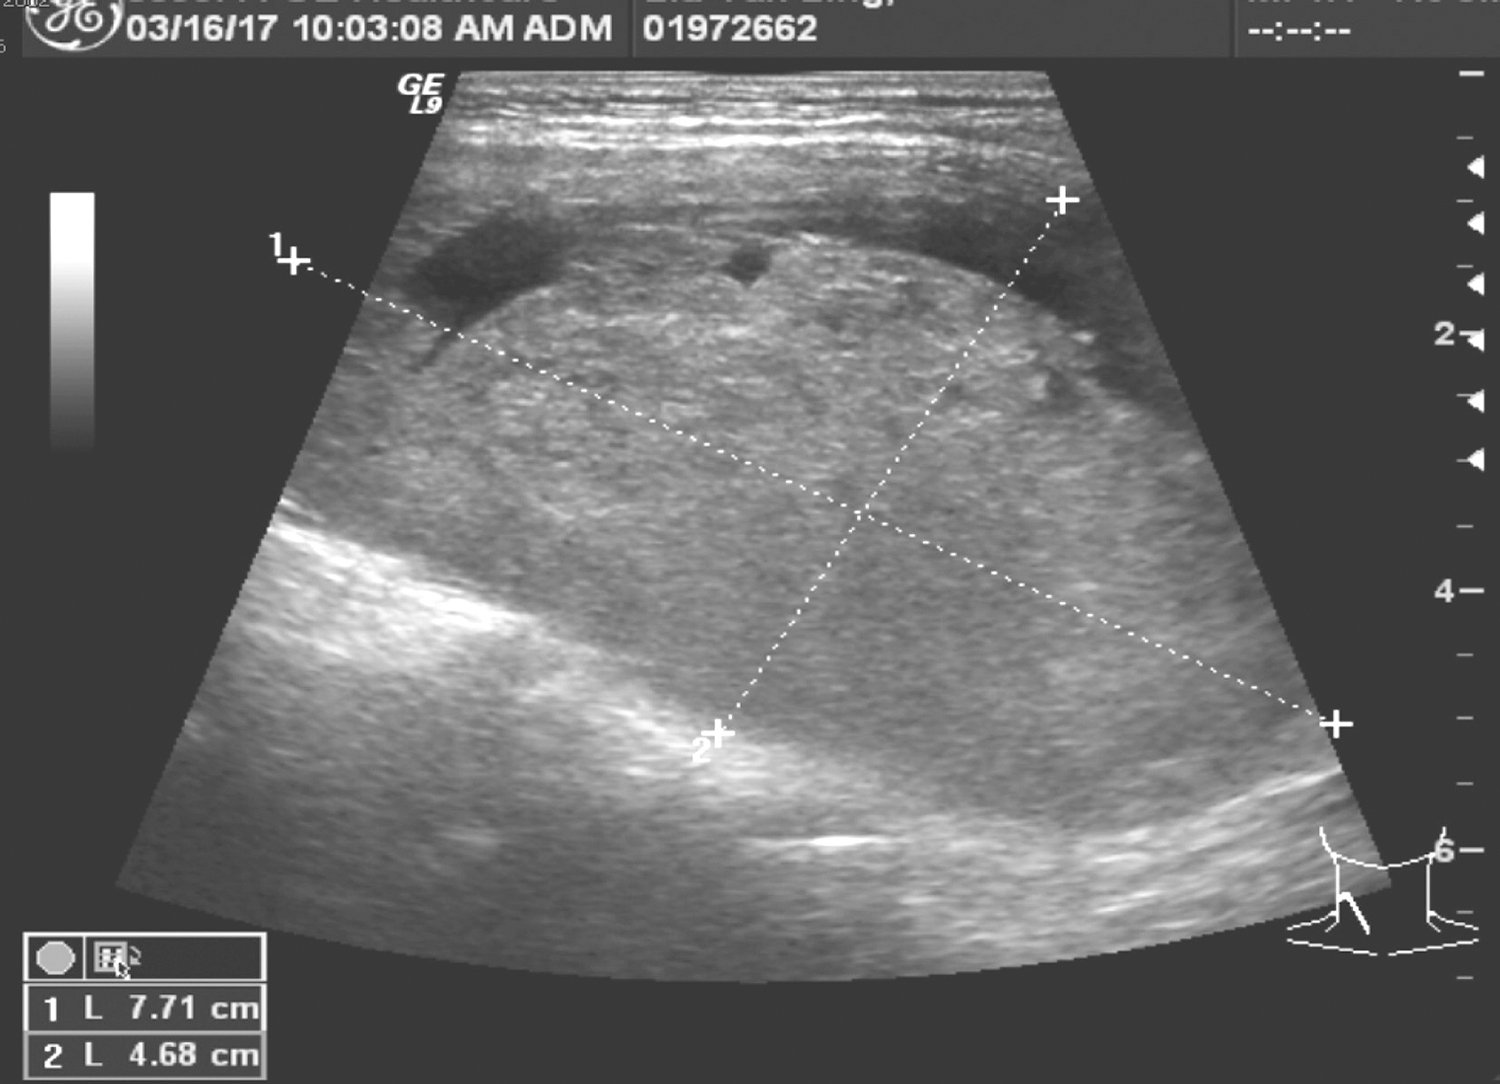

1.2017年3月16日颈部超声

甲状腺右叶体积明显增大,下极探及混合回声肿物,约7.7cm×4.7cm,边界尚清,CDFI探及少许血流信号(图1);甲状腺峡部未见明确占位;甲状腺左叶探及多个混合回声结节,大者位于中部偏上极,约1.0cm×0.8cm,边界清楚,CDFI探及少许血流信号;另甲状腺左叶上极探及低回声结节,范围约0.7cm×0.5cm,边界欠清楚,回声不均,可探及点片状强回声,CDFI探及少许血流信号;双侧中颈部探及低回声结节,右侧大者约1.0cm×0.6cm,左侧大者约1.3cm×0.8cm,边界清楚,淋巴门结构显示欠清楚,CDFI探及少许门样血流信号,余双颈部及锁骨上未见明确异常肿大淋巴结。

超声诊断:

(1)甲状腺右叶囊实性肿物,倾向良性。

(2)甲状腺左叶上极含钙化实性结节,建议密切随访或结合穿刺;余囊实性结节,倾向良性。

图1 颈部超声示甲状腺右叶下极肿物

(3)双侧颈部淋巴结,定期复查。